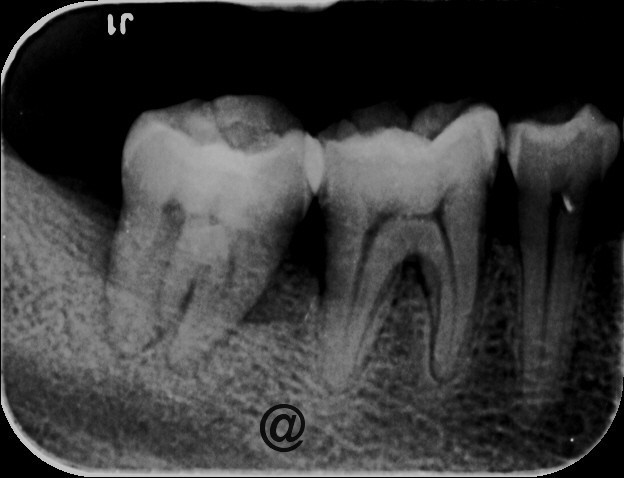

检查:右下7牙冠完整,近龈缘可见一突起脓包,少量脓血分泌物溢出,PD=10mm,余位点PD=3mm左右,叩痛(+),松动I度,电活力测试较正常牙迟钝。X线示:右下7牙槽骨水平吸收至根中,根分歧下低密度影像,远中根管增宽,可以根折。复拍CT:右下7根分歧下低密度影像,未达根尖,两根在舌侧融合,唇侧分开,唇侧无根柱,未见根折。